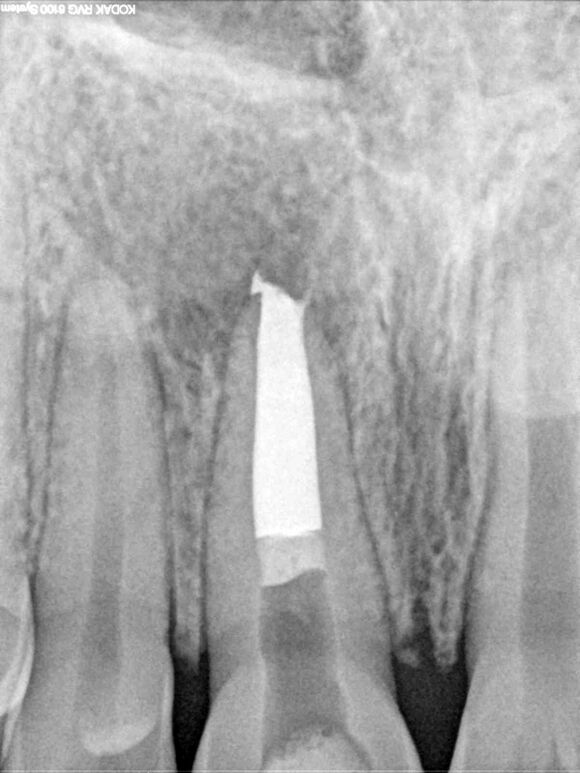

Beispiel 2: Vorher

Ausgedehnte Entzündung neben einem Implantat, bei diesem Überweisungsfall.

Beispiel 2: Nachher

Nur 6 Monate später ist die Entzündung fast vollständig zurückgegangen - Zahn und Implantat sind gerettet.